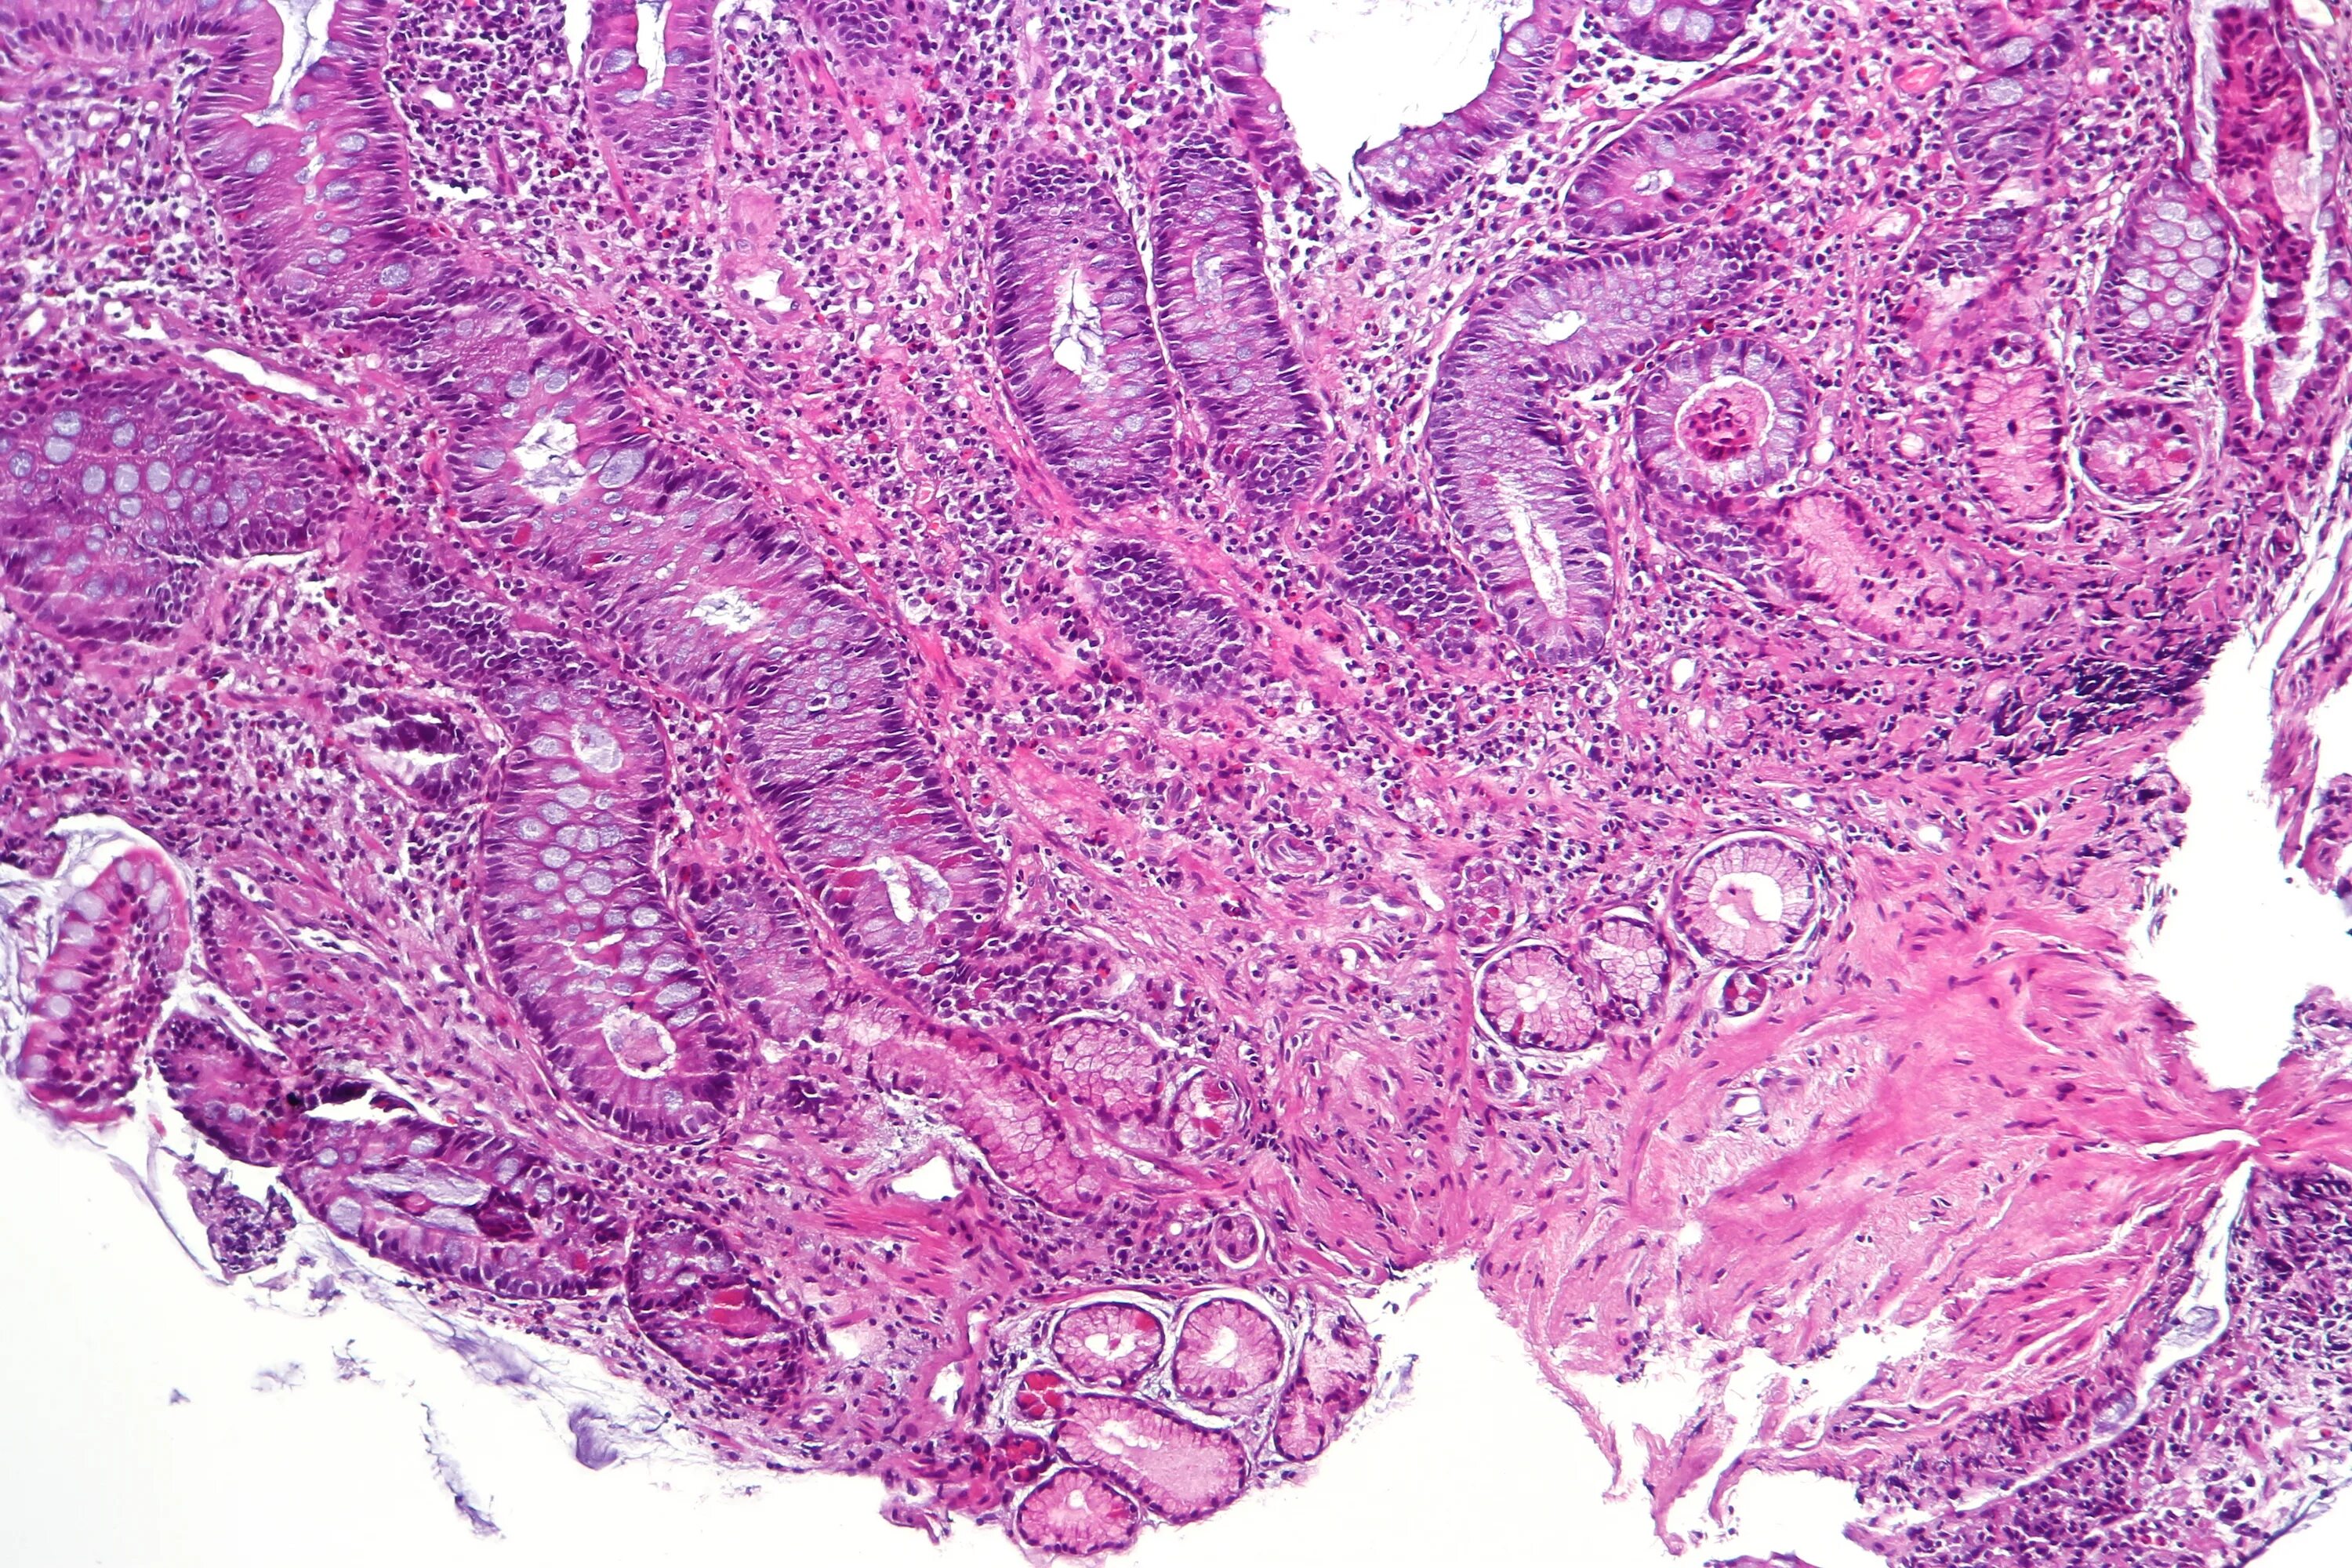

Кишечная метаплазия эпителия желез